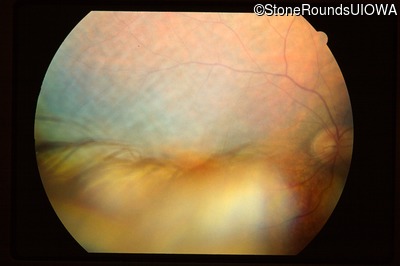

Fundus Photography - Right - Hand Motion sc

Exemplar

Fundus Photography - Left - Hand Motion sc

Fundus Montage - Right - Hand Motion sc